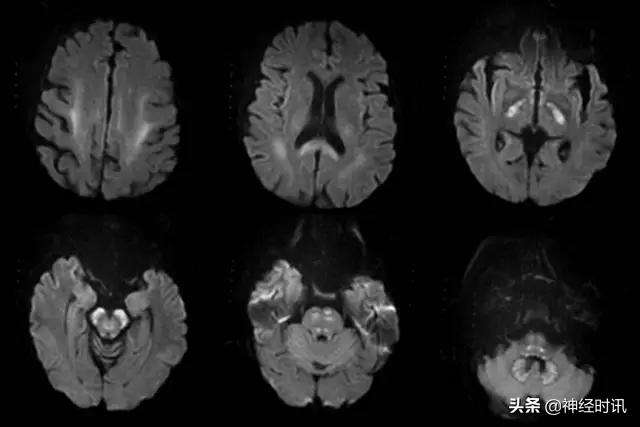

缺血缺氧性脑病

缺血缺氧性脑病(HIE)是全脑缺氧的结果。最常见的原因是心脏骤停、呼吸衰竭和休克。严重的患者大脑皮质和深部灰质均受累(图7)。较轻的患者可以见到边缘带梗死类型。罕有纯白质型,这可能是全脑缺血诱发脱髓鞘表现。小脑通常不受累。

图7 一例31岁男性,有*洛因海**和*卡因可**滥用史,出现无脉性电活动心搏骤停。MRI显示双侧顶枕叶和额叶、双侧丘脑弥漫性弥散受限(A:DWI,B:ADC)、T2-FLAIR高信号(C:FLAIR),符合全脑缺氧性损伤。